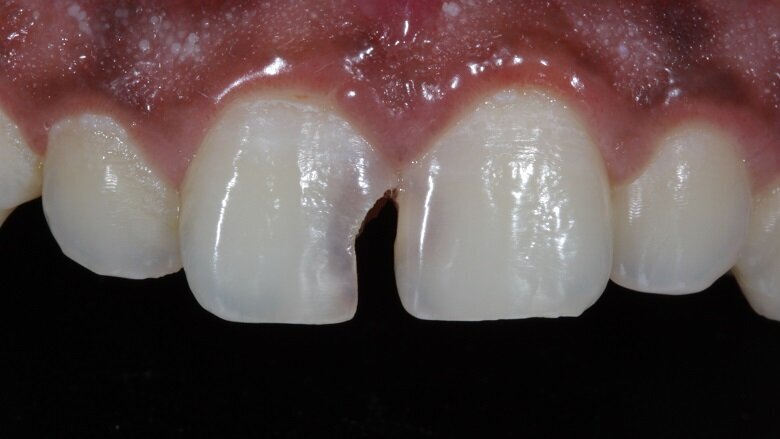

A 21 year old male reported to the clinic with a chief complaint that he was unhappy with his smile as he had a gap in between his front two teeth. He wanted a quick fix and had high aesthetic demands. Pre-operative photographs were taken at this point (Fig 1). On examination, tooth 11 showed decay mesially all the way extending upto the incisal edge (Class IV cavity). Tooth 21 also showed mesial decay only from the palatal aspect (Class III cavity).

Vitality test was performed and the result was positive, thus no endodontic treatment was required. Pre-operative analysis showed that due to a longstanding decay on 11 , 21 tipped mesially. This resulted in a slight shift in midline (Fig 2). On measuring the mesio-distal width of both the central incisors, they showed a discrepancy (Fig 2).